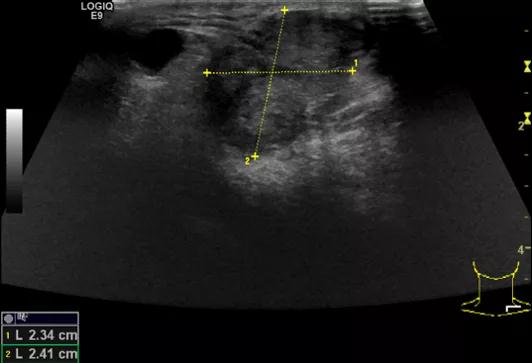

第二例是食管癌患者,术后半年余锁骨上固定淋巴结可触及肿大,疼痛非常明显,系统治疗后无缓解,患者希望通过局部处理缓解症状。造影显示强化信号明显,结节部分区域坏死,故主要针对强化区域从后向前的逐层的消融,皮下进行液体隔离减少烫伤。热消融后影像显示血流增强消失,弹性、硬度增高,一个月后复查显示充盈缺损,完全消融,疗效远超预期。

(病例2图例)